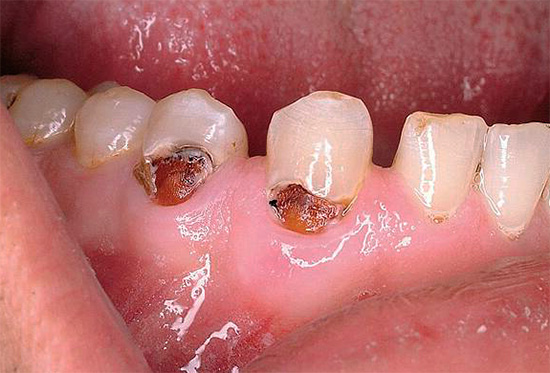

Abaixo estão algumas fotos com exemplos de cárie cervical:

A foto a seguir mostra claramente a cárie profunda na região cervical: